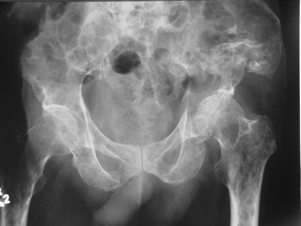

Fibröz Displazi

Fibröz displazi, normal kemik dokusunun yerini proliferatif fibröz dokunun alması ile karakterize kemiğin selim tümörüdür. Kemiğin medullar kanalından kaynaklanır. Görülme yaşı ergenlik çağı ve 20’li yaş grubudur.Monostotik ve poliostotik fibröz displazi olarak iki tipi vardır.Monostotik olanların oranı %70 dir.

Lezyon; kol ve bacak uzun kemiklerinde, kaburgada, leğen kemiğinde ve kafa-yüz kemiklerinde görülebilir. Monostotik fibröz displazi iskelet sistemi gelişmesi esnasında, poliostotik olanlar ise iskelet sistemi geliştikten sonra ortaya çıkar. Poliostotik olanların %2-3’ü endokrin rahatsızlıklarla birliktedir, ciltte sütlü kahverengi lekelerle birlikte çok kemikte lezyon var ise McCune-Albright sendromu denir. İntramusküler miksoma ile birlikte görülürse Mazabraud Sendromu denir.

Kemikte aşırı zayıflık oluşunca patolojik kırık gelişebilir. Uyluk kemiği üst ucunda lezyonun geliştiği fark edilmez ise çoban asası görüntüsü meydana gelir. Düz grafide buzlu cam görüntüsü tipiktir. Genellikle hastaların şikayeti yoktur. Şişlik ve ağrı şikayeti gelişebilir. Fibröz displazi iskelet sisteminin gelişimi ile birlikte büyür. İskelet büyümesi tamamlanınca lezyonun gelişimi yavaşlar.

Fibröz displazinin altı aylık aralarla alınacak filmlerlekontrolu yapılır. Bifosfanatlar medikal tedavide altın standarttır. Patolojik kırık veya patolojik kırık gelişme ihtimali yüksek olduğunda kanal içi çivileme ile tedavi edilir. Deformite geliştiğinde düzeltici osteotomi ve internal osteosentez uygulanır. Cerrahi tedavide; küretaj +grefonaj, yüksek nüks nedeni ile gözardı edilir, kanal içi osteosentez uygulanır. Ayrıca deformitenin gelişmesini engellemek için de geniş lezyonlarda koruyucu internal fiksasyon da yapılır. Büyüme kıkırdaklarının aktif olduğu dönemlerde intramedüller çivileme bu bölgelere zarar verebilir. Tedavide amaç deformitelerin oluşmasını engellemek ve var olanı düzeltmektir. Monostotik formlarda %0,4 oranında kötü huylu tümöre (malignite) dönüş bildirilmiştir.